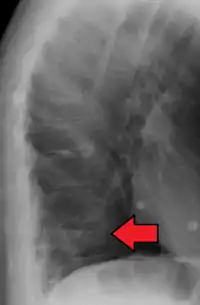

X-ray of the lumbar spine with a compression fracture of the third lumbar vertebra.

A compression fracture is a collapse of a vertebra. It may be due to trauma or due to a weakening of the vertebra (compare with burst fracture). This weakening is seen in patients with osteoporosis or osteogenesis imperfecta, lytic lesions from metastatic or primary tumors,[1] or infection.[2] In healthy patients, it is most often seen in individuals suffering extreme vertical shocks, such as ejecting from an ejection seat. Seen in lateral views in plain x-ray films, compression fractures of the spine characteristically appear as wedge deformities, with greater loss of height anteriorly than posteriorly and intact pedicles in the anteroposterior view.[3]

Compression fractures are usually diagnosed on spinal radiographs, where a wedge-shaped vertebra may be visible or there may be loss of height of the vertebra. In addition, bone density measurement may be performed to evaluate for osteoporosis. When a tumor is suspected as the underlying cause, or the fracture was caused by severe trauma, CT or MRI scans may be performed.